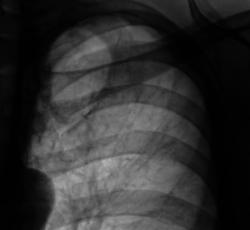

При расшифровке цифровых флюорограмм "пациент взят на контроль". Жалоб пациент не предъявляет. Произведено стандартное дообследование - рентгенография и томография.

Кальцинаты, инуративные очаги в зоне пневмосклероза. Отзвучавший туб. процесс. Больше пока не вижу.

В таком случае, Валентин Львович, Вы подтвердили мои сомнения по поводу активности процесса. 2 года назад норма, а теперь такая картина. Это активный процесс. Выраженный пневмосклероз в виде "сетки" в целой доле. Пациента необходимо направить к фтизиатрам.